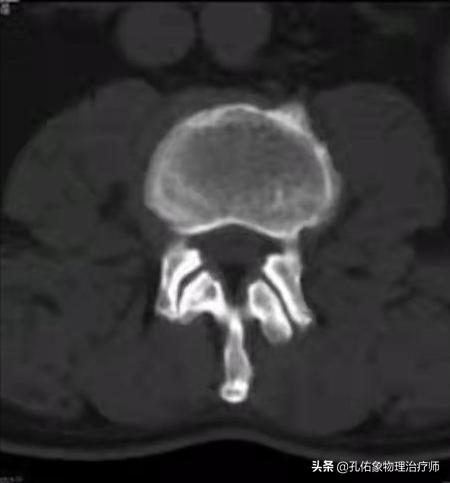

如上图中所示, 椎管在椎间盘(髓核+纤维环)的后方,里面穿行脊髓;若是因为某种因素使椎管变窄了,很可能会压迫神经、脊髓等。

腰椎的椎体后缘增生,后纵韧带的钙化,小关节突增生,侧隐窝狭窄,黄韧带肥厚,椎管内占位(肿瘤或间盘脱出)。